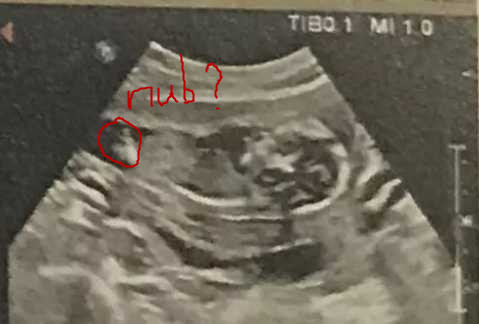

Please guess my friend's 12 week scan thanks.Attachment 42410

This is the only pic she has. Is this nub?Attachment 42411

It is the nub area, but the area between the nub and the belly is missing, its kind of hollowed out in that bit which is te detail i would need to know if the white bit is the tip of a nice flat white line as there is just a shadow of a flat line or if that is showing some very low in the body stacking:) I will try and draw on what I mean later on if thats ok :)

I would guess boy from this, but it's not very clear.